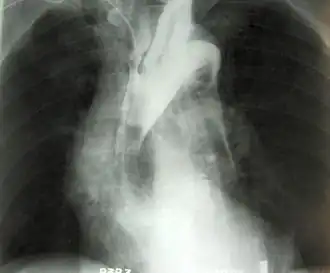

Anevrismul reprezintă o formațiune vasculară cu aspect tumoral, localizată pe traiectul unei artere (cel mai des) sau vene[1]. Se prezintă ca o dilatare (ca un sac) a vasului sanguin și poate fi localizat oriunde în organism[2]. Cu toate acestea, cel mai adesea el se dezvoltă în segmentul abdominal al arterei aortice și la nivelul vaselor creierului (anevrism cerebral)[3]. În majoritatea cazurilor este asimptomatic.